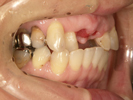

50代女性

![]() |

治療前 |

||

治療中。仮歯。 左上の奥にインプラント埋入。 噛みあわせ治療を行いました |

治療後 全体の歯で食事がおいしくできるようになったと喜んでおられました。 |